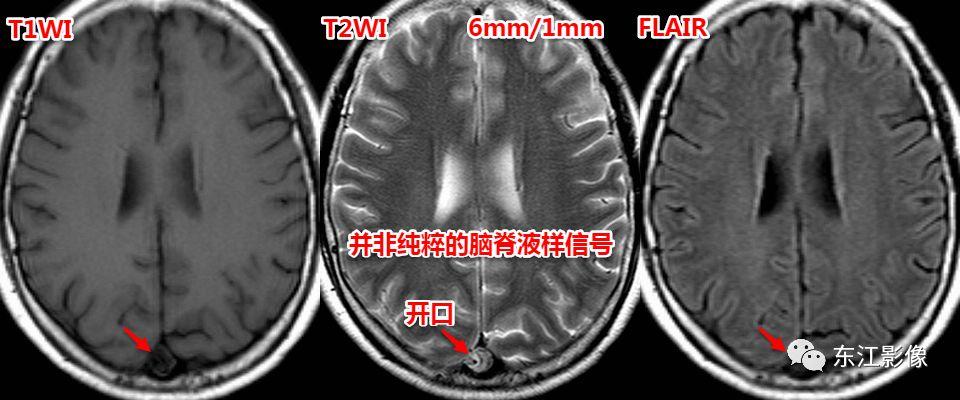

5. 脑脊液流动伪影

- 脑脊液流动伪影主要见于T2WI、FLAIR,主要是长TE序列容易出现流空效应的缘故。

- 但由于脑脊液流动方向、速率不一等因素的影响,呈现为非脑脊液信号影像,部分呈囊样。

- 常见于第三脑室、侧脑室室间孔旁区、脑干周围脑池(这些区域结构复杂)。

- 鉴别要点,T1WI、增强未能辨认;DWI与邻近一致的无信号;无占位效应。

侧脑室室间孔旁脑脊液流动伪影。

又一例。